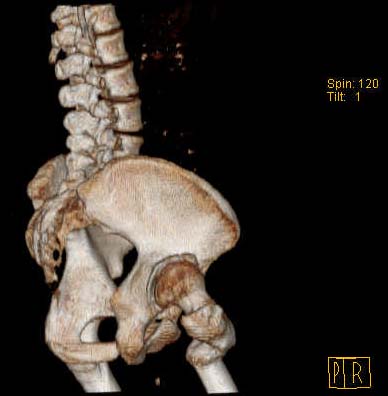

Уважаемые коллеги!Женщина, 35 летВ прошлом по поводу врожденного вывиха бедра перенесла операцию остеотомии по Шанцу

с удлинением правой ноги за счет бедра на уровне диафиза. В последнее время прогрессируют боли в правом тазобедренном суставе, порочное положение правой ноги, затруднена ходьба.Вопросы:1) Целесообразно ли эндопротезирование правого тазобедренного сустава?2) Целесообразный ли следующие действия: канал бедренной кости предполагаем вскрыть для введения ножки протеза на высоте угловой деформации, предполагаем низведение большого вертела с мышцами; протез будет подобран индивидуально, предполагается умеренная версия?В приложении рентгенограммы и трехмерная КТ.В цветном и более качественном варианте КТ размещена здесь

2. К сожалению, техника операции, представленная коллегами из Москвы здесь не получится, т.к. остеотомия бедренной кости была выполнена достаточно низко (по отношению к области сустава). На мой взгляд, целесообразно выполнить остеотомию на высоте деформации с основанием клина кнутри (что бы не было дефекта кости)и ввести понопокрытую ножку с проксимальной и дистальной фиксацией (по типу AML, ее длина 180 мм, при необходимости можно и 200 мм, надо рассчитать). Стабильность ножки будет обеспечена дистальной ее фиксацией, если будут сомнения относительно прочности фиксации короткого проксимального фрагмента, то линию остеотомии можно перекрыть кортикальными аллографтами.